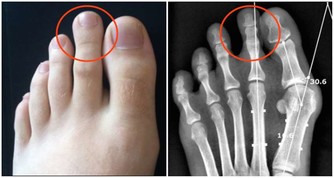

一般來說,成年人每天需要55微克硒,孕婦或母乳喂養的女性分別需要60和70微克。如果你營養均衡,可以在飲食中得到足量的硒,但問題是很多人的營養並不均衡。那麼,讓我們通過下面的跡象來判斷你是否缺硒吧。